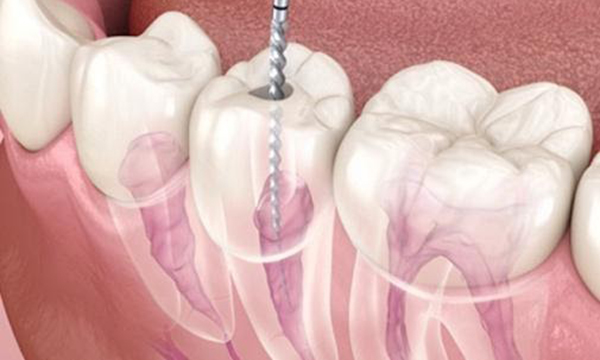

針のような道具を使って、感染した汚染物をとりのぞいていきます。

抜髄の流れ

3. 針のような道具を使って、歯の神経を

取り除く

2. 針のような道具をつかって神経の穴の中の感染物を取り除く